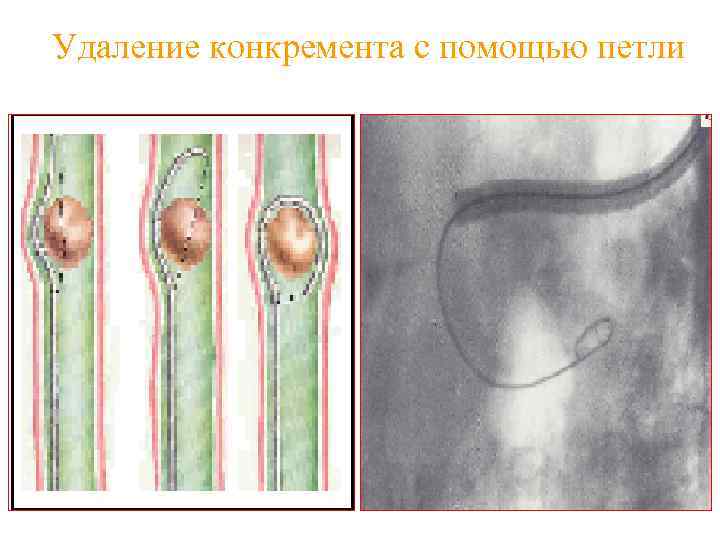

Удаление конкремента с помощью петли